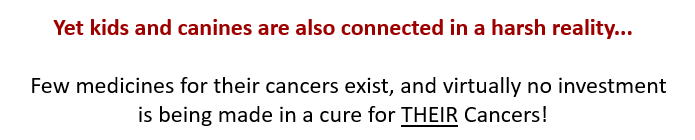

Did you know?

There are several cancers that develop spontaneously both in dogs and kids including

- bone cancer

- certain brain/central nervous system cancers (e.g. glioma, glioblastoma)

- lymph and blood cancers

And these are often different from cancers in adult humans. How these cancers develop, “behave” and progress, and even the side effects kids and canines experience from treatment, are very similar.